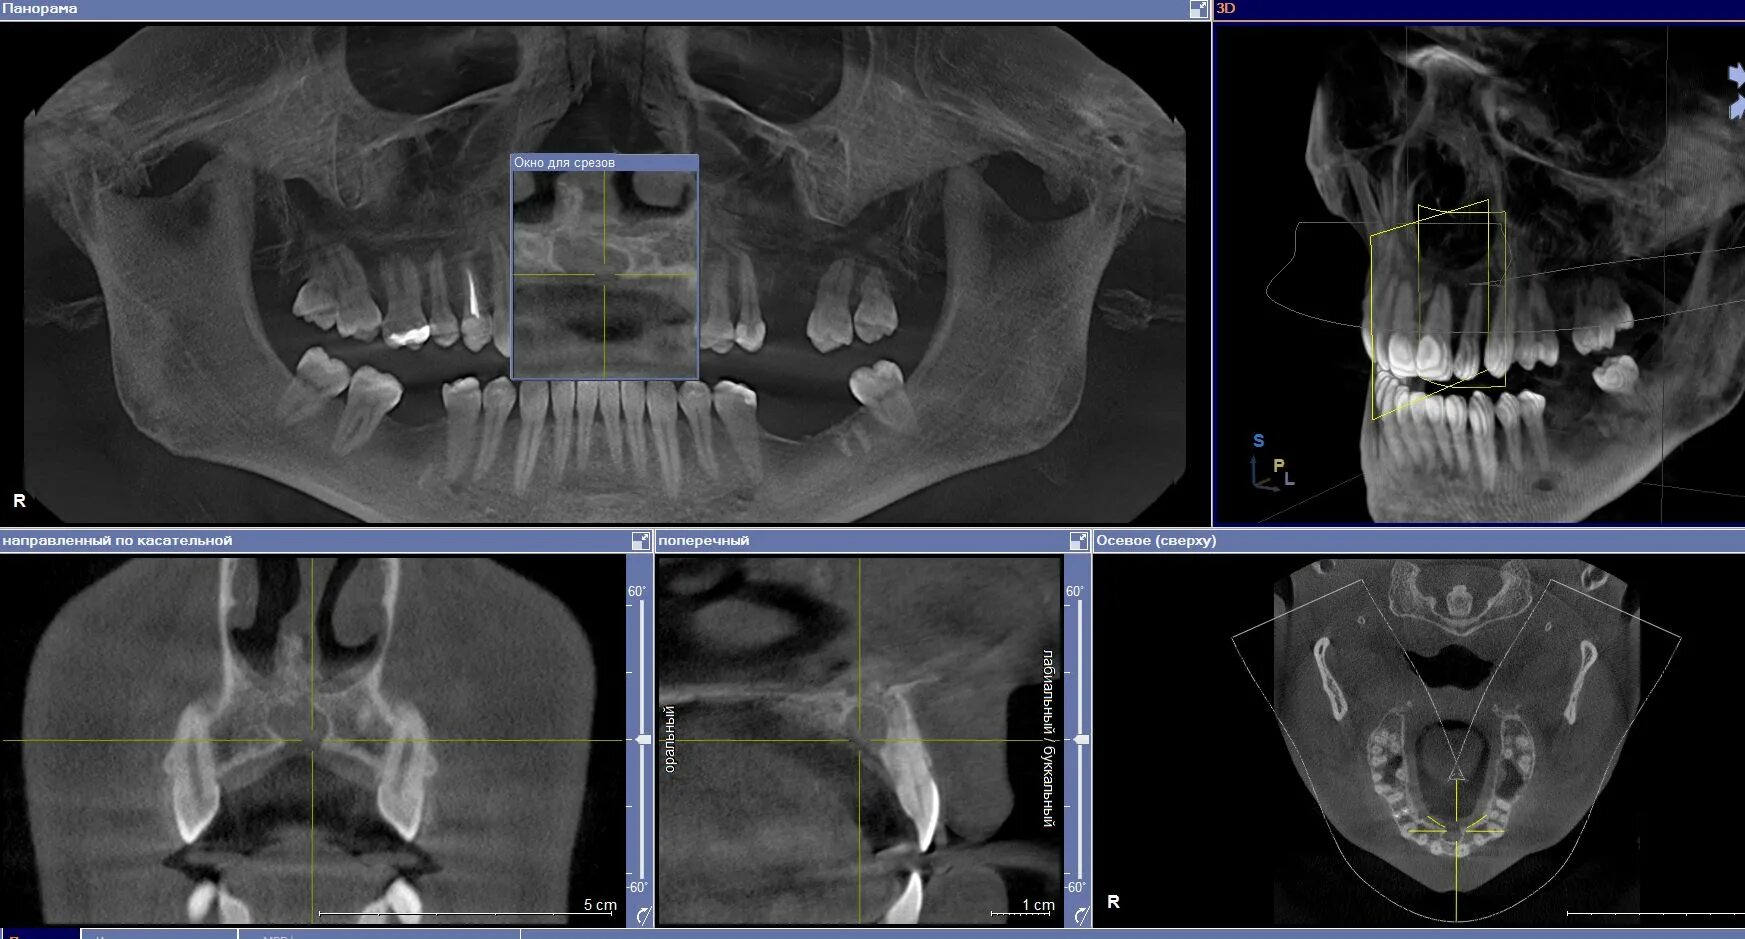

Операции челюстно лицевого хирурга